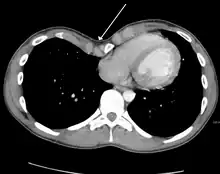

Cross sectional scan of a chest with pectus excavatum

Pectus excavatum is initially suspected from visual examination of the anterior chest. Auscultation of the chest can reveal displaced heart beat and valve prolapse. There can be a heart murmur occurring during systole caused by proximity between the sternum and the pulmonary artery.[15] Lung sounds are usually clear yet diminished due to decreased base lung capacity.[16]

Many scales have been developed to determine the degree of deformity in the chest wall. Most of these are variants on the distance between the sternum and the spine. One such index is the Backer ratio which grades severity of deformity based on the ratio between the diameter of the vertebral body nearest to xiphosternal junction and the distance between the xiphosternal junction and the nearest vertebral body.[17] More recently the Haller index has been used based on CT scan measurements. An index over 3.25 is often defined as severe.[18] The Haller index is the ratio between the horizontal distance of the inside of the ribcage and the shortest distance between the vertebrae and sternum.[19]